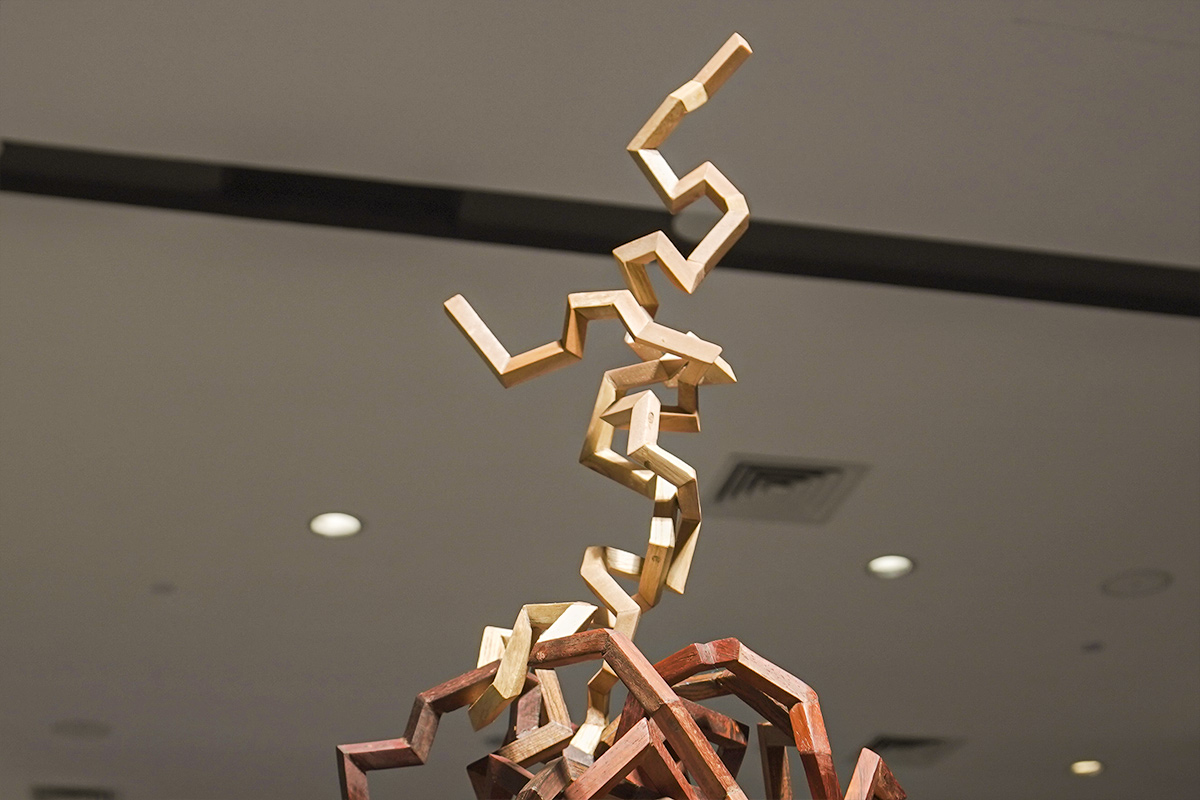

"Truth Capturer" ŌĆö Antigen-Antibody Detection Model Sculpture

This sculpture is now standing in the IVD exhibition hall at Mindray's headquarters. When you look at the sculpture closely, you can see that its central part is like an irregular "paper cluster" formed by interlaced three-color wooden pieces. It is held firmly by the Y-shaped "tentacles" at the upper and lower ends.

"Truth Capturer" ŌĆö Antigen-Antibody Detection Model Sculpture

This structure is inspired by the detection model of the cardiac marker ŌĆö troponin, where the detection and capture antibodies work together to capture antigen complexes. The combination of the beveled, flipped wooden pieces reproduces the dynamic, folded structure of the proteins.